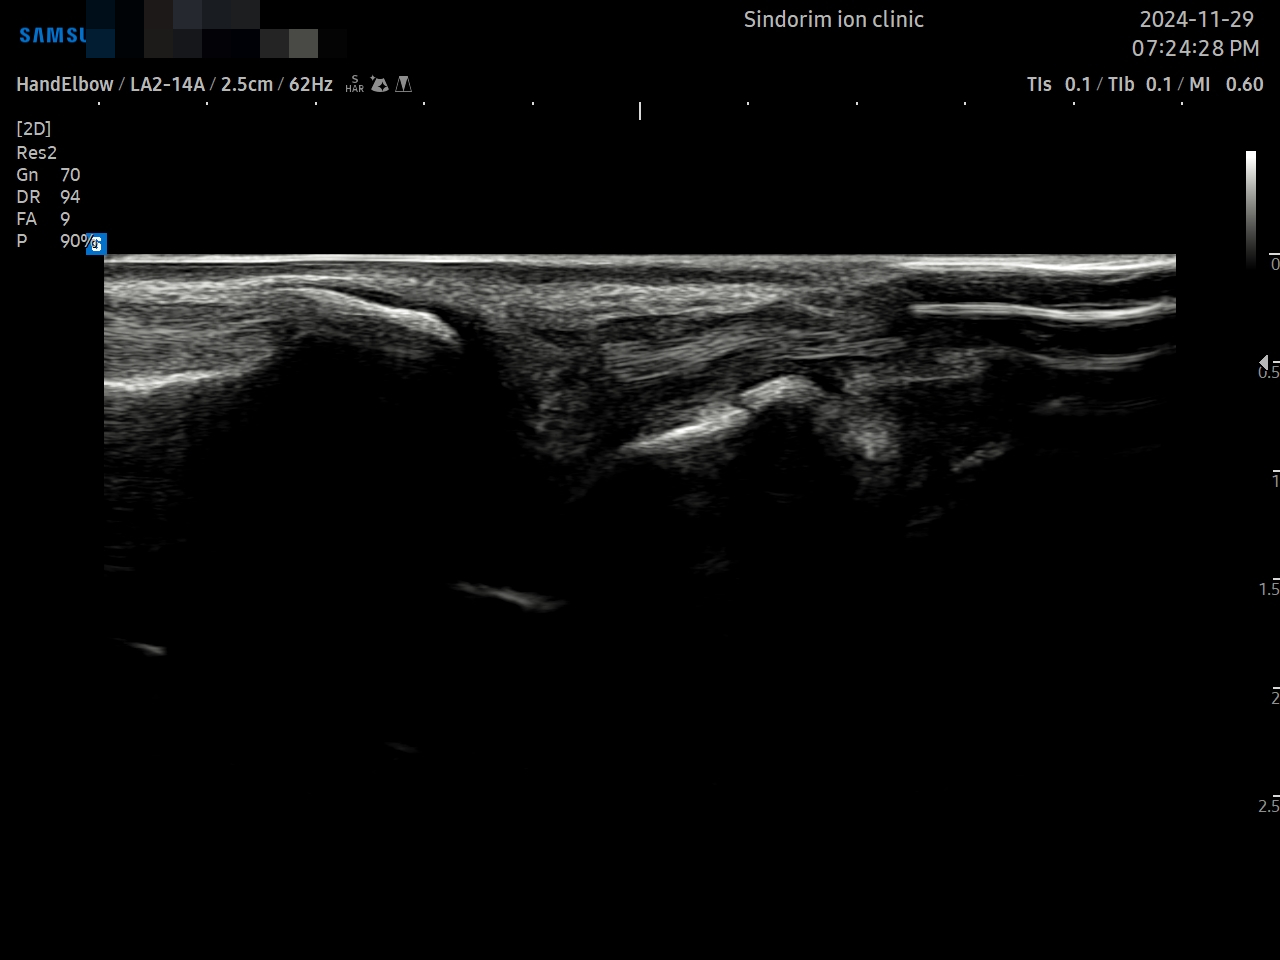

[치료 전]

TFCC 디스크

TFCC Meniscus, 인대

Compartment

[치료 후]

- 치료기간 : 2024 . 09 . 05 ~ 2025 . 03 .10.

- 치료횟수 : 30회+2cycle